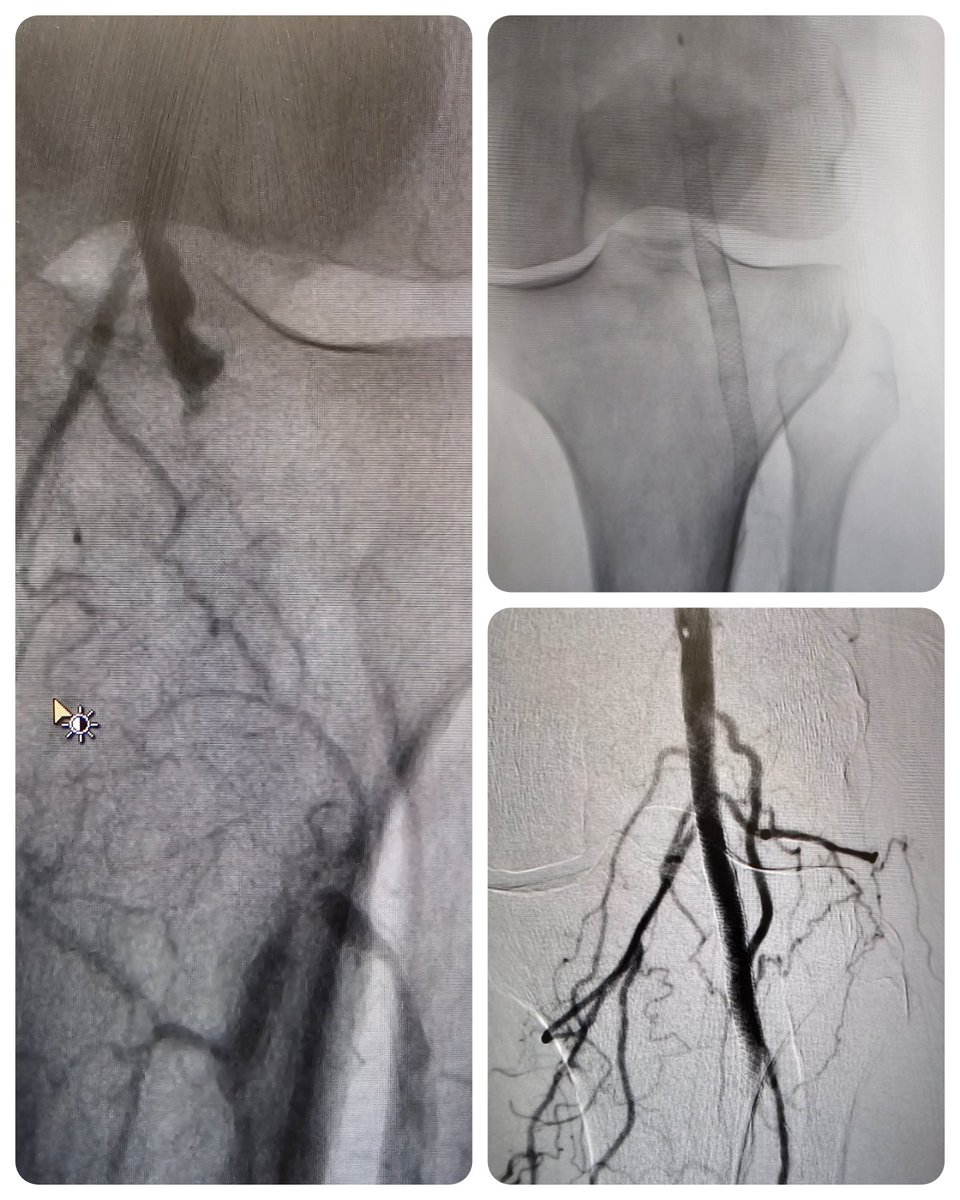

#CLTIfighters <60y.o male DM, failed CABG, ef 30% with RLE wound. Cannot get PTFE because of the wound location and risk of infection. ABI .27 angio below

PT with resting pain and toe ulcer, CTO of the popliteal artery. Successfully crossed and stented.

#supera #clifighter